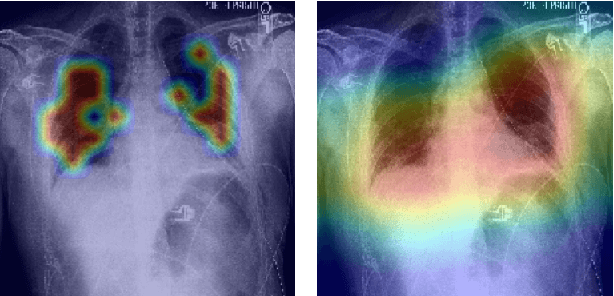

Abstract:Radiographs are a versatile diagnostic tool for the detection and assessment of pathologies, for treatment planning or for navigation and localization purposes in clinical interventions. However, their interpretation and assessment by radiologists can be tedious and error-prone. Thus, a wide variety of deep learning methods have been proposed to support radiologists interpreting radiographs. Mostly, these approaches rely on convolutional neural networks (CNN) to extract features from images. Especially for the multi-label classification of pathologies on chest radiographs (Chest X-Rays, CXR), CNNs have proven to be well suited. On the Contrary, Vision Transformers (ViTs) have not been applied to this task despite their high classification performance on generic images and interpretable local saliency maps which could add value to clinical interventions. ViTs do not rely on convolutions but on patch-based self-attention and in contrast to CNNs, no prior knowledge of local connectivity is present. While this leads to increased capacity, ViTs typically require an excessive amount of training data which represents a hurdle in the medical domain as high costs are associated with collecting large medical data sets. In this work, we systematically compare the classification performance of ViTs and CNNs for different data set sizes and evaluate more data-efficient ViT variants (DeiT). Our results show that while the performance between ViTs and CNNs is on par with a small benefit for ViTs, DeiTs outperform the former if a reasonably large data set is available for training.